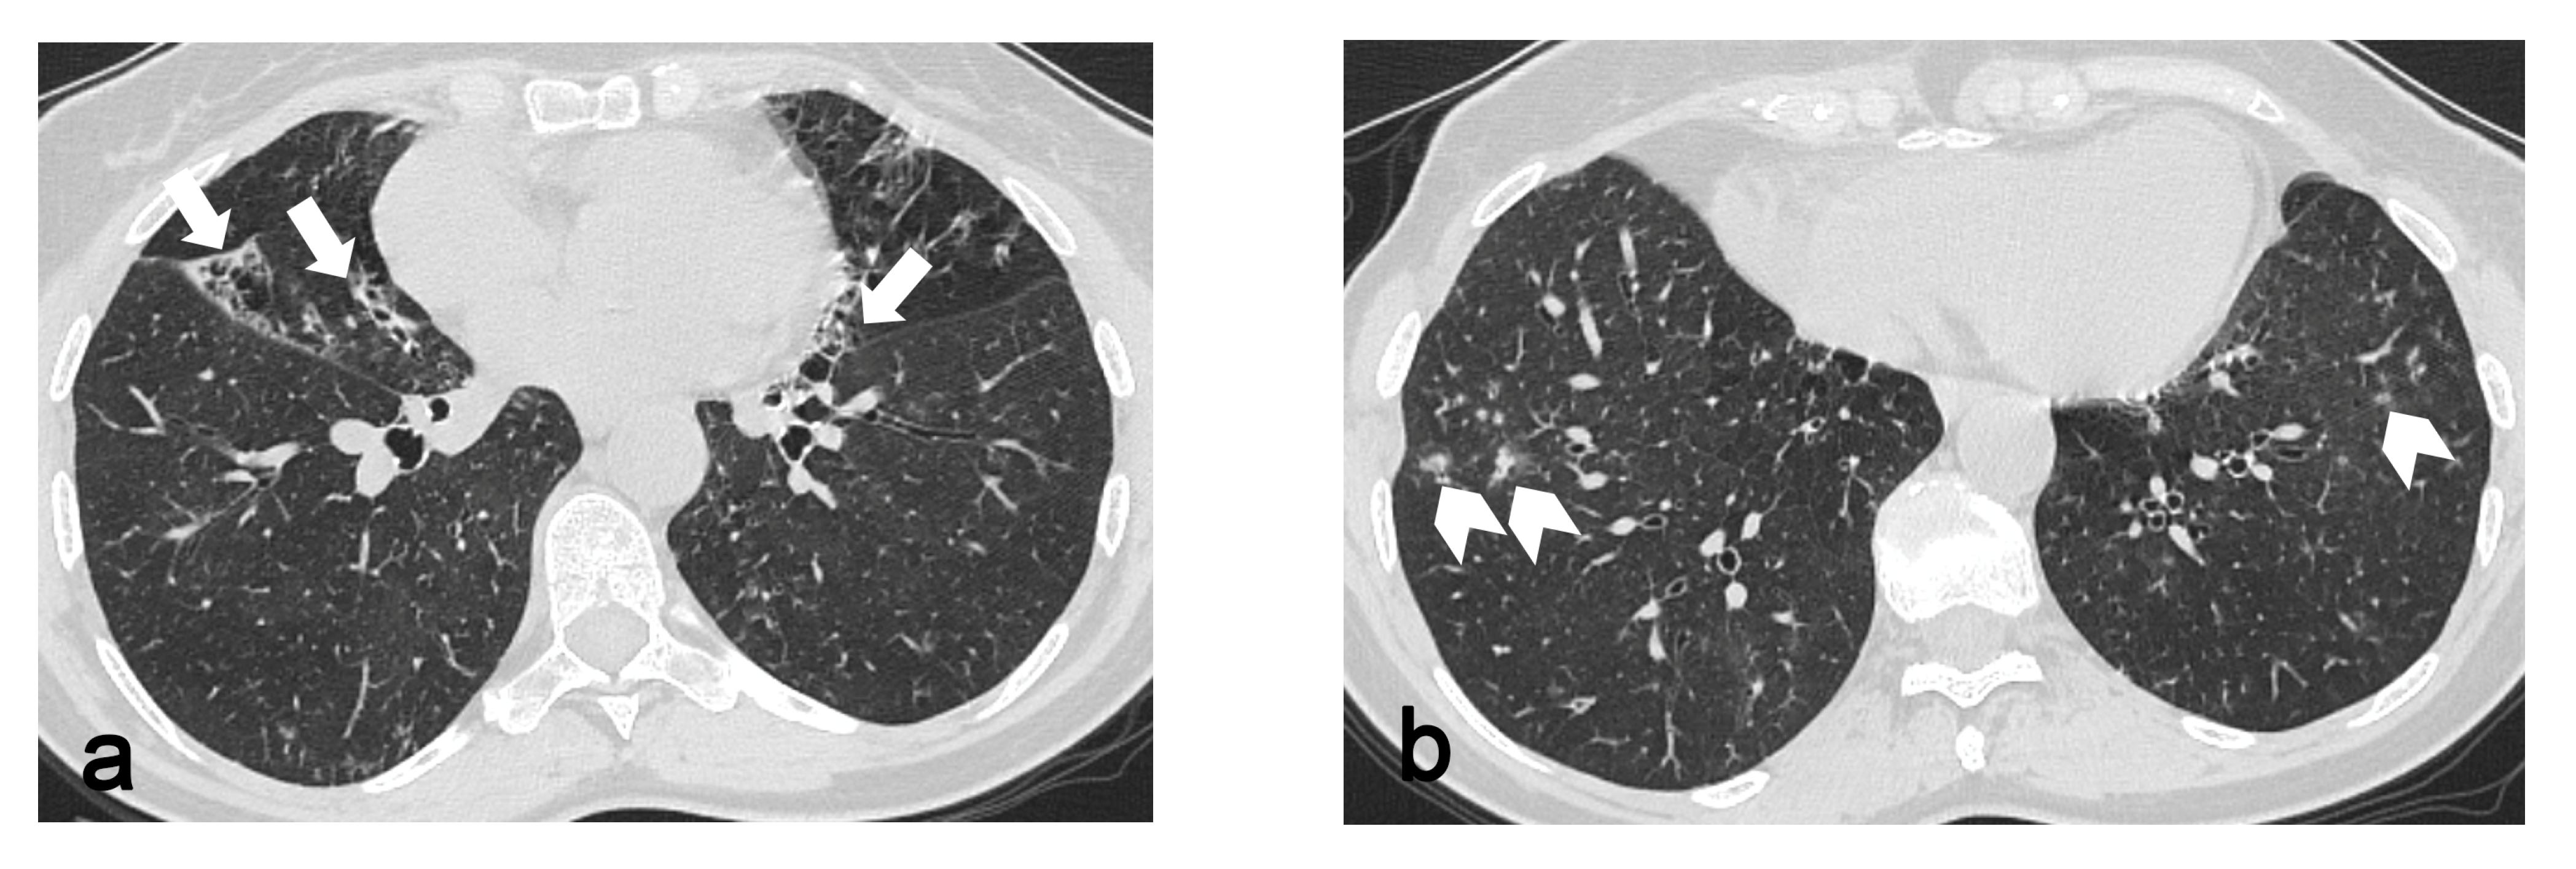

In 87 out of 106 patients without progressive disease, apart the involvement of the apical and or dorsal segments of the upper lobes, 39 exhibited an involvement of the apical segment of the RLL, 53 saw an involvement of the right fissure, 15 saw an involvement of the ventral segment of the RUL, 30 saw an involvement of the apical segment of the LLL, 52 saw an involvement of the left fissure, and 12 saw an involvement of the ventral segment of the LUL. On the other hand, regarding the 19 patients with an increased score between the first and the second exam, 17 exhibited an involvement of the apical segments of the lower lobes and fissures bilaterally, while 14 exhibited an involvement of the ventral segments of the superior lobes. Statistical analysis revealed a significant difference between the two groups (progressive vs. non-progressive disease) regarding the involvement of the ventral segments of the upper lobes (p = 8.09 × 10−7 and p = 5.71 × 10−8 for the RUL and the LUL, respectively), fissures (p = 0.02 and p = 0.01 for the right and left fissures, respectively) and apical segments of the lower lobes (p = 1.67 × 10−5 and p = 0.01 for the LLL and RLL, respectively), as shown in Table 2. Among these 19 patients exhibiting a worsening of PPFE-like alterations, 5 showed an associated fibrotic pattern that was “UIP consistent”, 1 of whom worked in a knitwear factory and 1 of whom was exposed to paints. In total, 4 patients showed only PPFE-like lesions, 1 of whom was affected by psoriatic arthritis, 1 who was exposed to asbestos and 2 who were affected by mixed connective tissue disease. In total, 3 patients showed bronchiectasis with infective chronic bronchiolitis, 2 of whom were detected as being positive at BAL for atypical mycobacteria (Figure 2). In total, 2 patients were affected by chronic extrinsic allergic alveolitis, one of whom was a hairdresser and the other a breeder of canaries. Two patients showed a concomitant emphysema.

Figure 2. Bronchiectasis (arrows in (a)) and infective bronchiolitis (arrowheads in (b)) in a 67-year-old woman affected by atypical mycobacteriosis and PPFE-like lesions, which involve upper segments of lower lobes, fissures and apico-dorsal portions of upper lobes (c,d). A follow-up exam after three years (e) shows a progression of PPFE-like lesions.